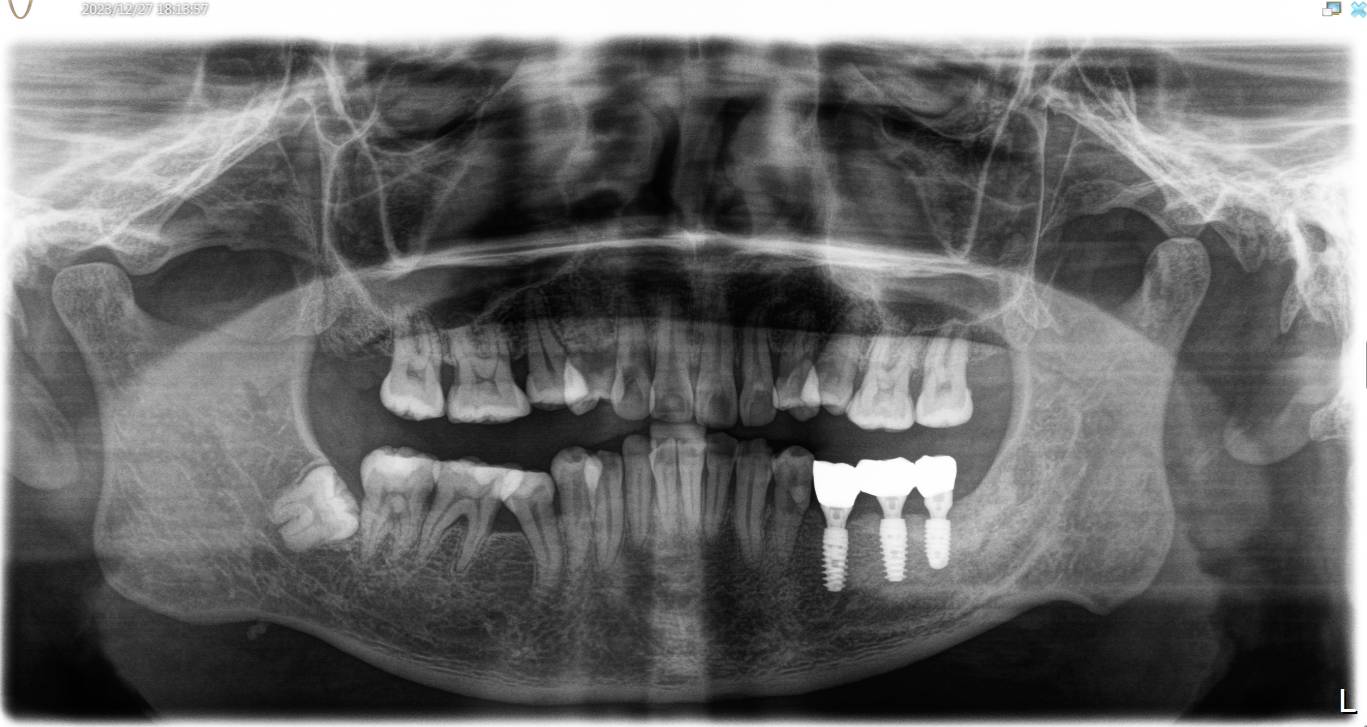

患者男,四十岁,全口口腔卫生较差。牙石+++,色素+++。左下后牙松动,X线示全口牙槽骨水平性吸收,35 36,37牙槽嵴吸收至根尖1/3。

患者自愿选择安卓健种植体。牙槽嵴吸收较多,高度和宽度不足。拔出后植入骨粉骨膜。待骨条件良好后。35植入种植体4.0*10mm;36植入种植体4.6*10mm;37植入种植体4.6*8mm。待骨结合良好后。二期三期如期进行。余近日戴牙。

术前